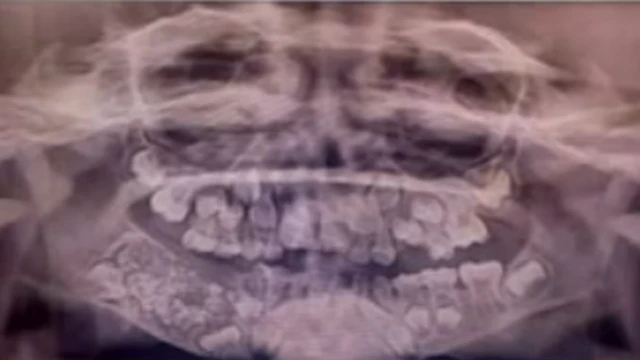

Anasema picha iliopigwa kwa kutumia miyale ya X-ray ilibaini meno mengi yaliowafanya madaktari hao kumfanyia upasuaji unasema mtandao wa Zee News.

Ijapokuwa kulikuwa na vipande vidogovidogo, madaktari wanasema kuwa vilikuwa na ishara ya meno. Ilichukua takriban saa tano kwa madaktari hao kutoa meno hayo madogo kutoka katika kifuko hicho.